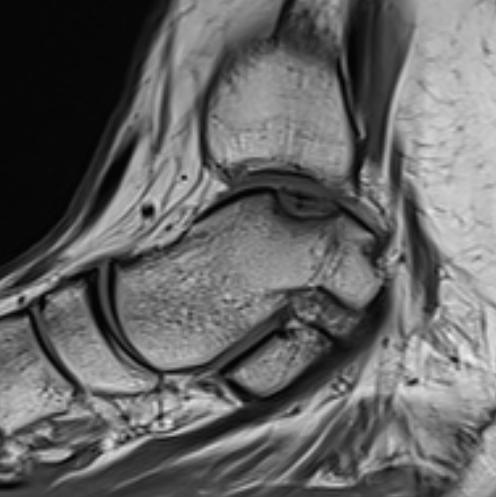

MRI

Stable lesion (Stage I) - cartilage intact, no synovial fluid under lesion

Unstable lesions (Stage II or III) - cartilage breach, synovial fluid under lesion

Displaced lesion with resultant osteochondral defect

Stable lesion with intact cartilage and no synovial fluid under lesion

Stage III completely detached but not displaced